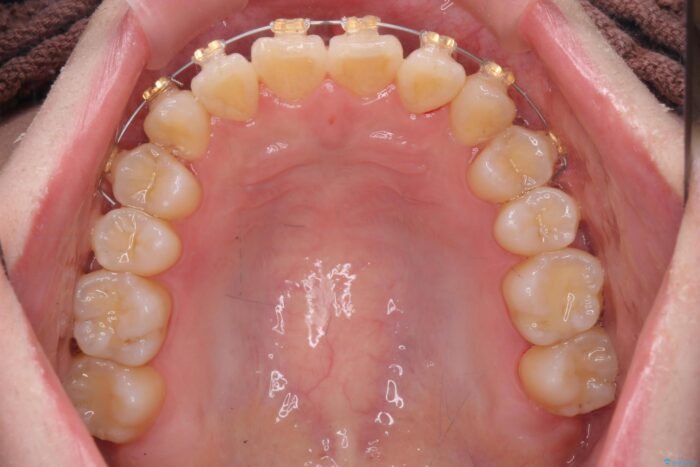

インビザライン +部分ワイヤー矯正

前歯のねじれが気になる、歯並びを改善したいとご来院された患者様です。

歯のねじれをきれいに取るのは、インビザライン(マウスピース矯正)だけでは難しい動きです。そのため、事前に4か月間の部分ワイヤー矯正を行い、治療期間を短くし、より美しい仕上がりを目指す計画です。

前歯が綺麗に並び、大変ご満足いただけました。